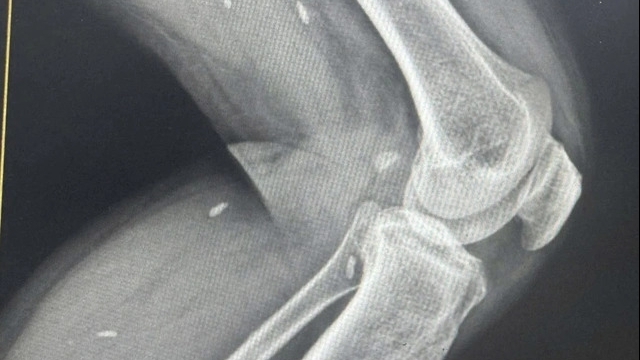

Tại đây, 100 đối tượng chính sách là các thương binh, bệnh binh, người hoạt động kháng chiến bị nhiễm chất độc hóa học, thân nhân các gia đình liệt sỹ đã được các y, bác sĩ thuộc Trung tâm y tế huyện Mỹ Đức thực hiện khám, tư vấn chăm sóc sức khỏe, lập hồ sơ theo dõi, quản lý sức khỏe định kỳ và được khám chuyên sâu về các chuyên khoa: khám lâm sàng chuyên khoa nội, ngoại, răng hàm mặt, tai mũi họng, siêu âm, điện tim, xét nghiệm sàng.

| Siêu âm ổ bụng cho đối tượng chính sách trên địa bàn xã Hùng Tiến |